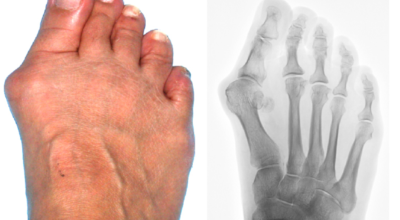

무지외반증은 엄지발가락이 두 번째 발가락 쪽으로 심하게 휘어지며 관절이 안쪽으로 튀어나온 것을 말합니다. 무지외반증은 발가락이 단순히 휘는 정도가 아니라 튀어나와 통증을 일으키는 병입니다. 따라서 발의 볼은 넓어지며, 조금만 조이는 구두를 신어도 통증을 느끼게 됩니다. 또 엄지발가락이 두 번째 발가락을 밀어 둘째 발가락도 함께 변형되어 뒤틀어진 변형을 만들 수 있답니다.

변형이 악화되면 엄지발가락이 두 번째 발가락과 겹치거나 관절이 탈구되어 전반적으로 디디기 어려운 발이 되기도 합니다. 건강보험심사평가원의 무지외반증 환자 통계를 보면, 세대별로는 40대 이상에서 가장 많고 성별로는 무지외반증 여성 환자 비율이 남성보다 월등하게 높았다고 해요.

무지외반증은 발가락의 휘어짐 정도로 1단계 ~ 4단계까지 나눌 수 있어요.

1단계 : 15도 ~ 20도 휘어짐, 외관상 변화가 심하지 않음

2단계 : 20도 ~ 30도 휘어짐, 외관상 변화가 확연히 보임

3단계 : 30도 ~ 50도 휘어짐, 2, 3번째 발가락에 변형이 나타남

4단계 : 50도 이상 휘어짐, 정도가 심한 변형과 극심한 통증이 나타남, 정상적인 보행이 어려움

1, 2단계는 경증으로 통증이 나타나지 않으나, 3단계부터 신발을 신거나 쓸리고 눌릴 때마다 통증이 발생합니다. 4단계는 두번째 발가락이 엄지 발가락 위에 높아져 있다고 하며 뼈의 돌출이 심해진 상태라서 극심한 통증을 동반해서 신발을 신는 것 자체가 불편해지기도 합니다.

무지외반증은 외형적인 변형만으로 진단이 가능하며 적절한 치유하기 위해 의사의 진찰 또는 방사선 촬영 검사를 진행합니다. 치료 여부는 환자의 불편 정도와 의학적 소견을 종합해서 결정합니다.